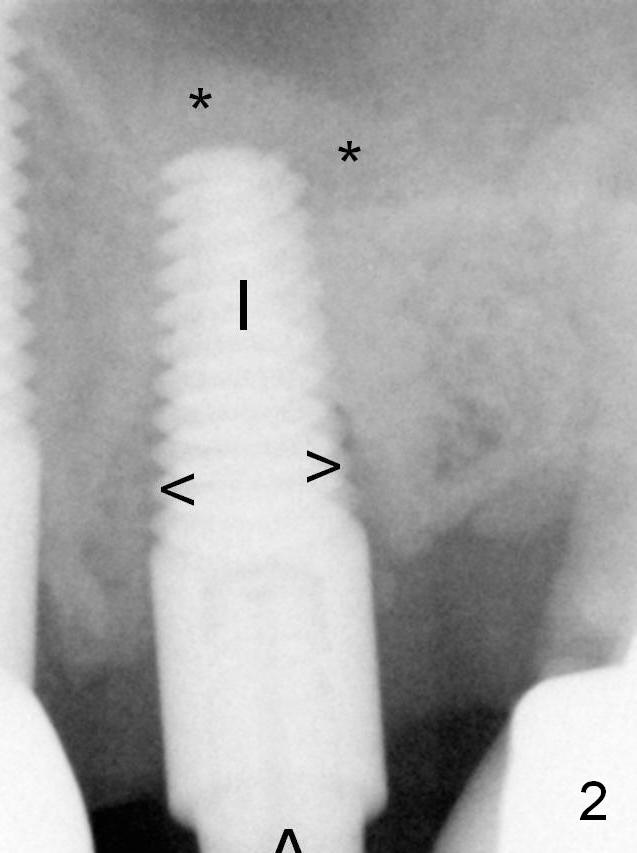

There is no sign of sinus membrane perforation before placement of a 4.5x14 mm implant (Fig.2 I); sinus lift is performed (*, with mixture of autogenous bone (from reamers), allograft and Osteogen). Arrowheads: remaining mesial and distal sockets, which will be bone grafted after provisional fabrication.